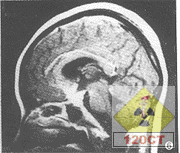

急性硬腦膜下血腫2.頭部CT應作為首選檢查專案,具有簡便、安全、可在短時間內顯示血腫的位置、大小和數目等優點,對於額葉底、顳葉底和兩側性血腫的診斷往往較腦血管造影更具有優越性,可以減少血腫的漏診。

CT掃描內板下透鏡狀高密度影硬腦膜下及腦內不規則高密度影病變區呈低密度影。